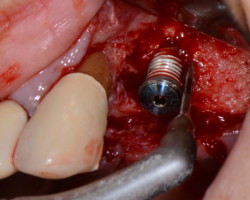

- Phase correctrice : créer des conditions compatibles avec la maintenance. (chirurgie résectrice, implantoplastie, correction prothétique)

- Phase réparatrice: Réduire la profondeur de poche et réparer les tissus détruits.